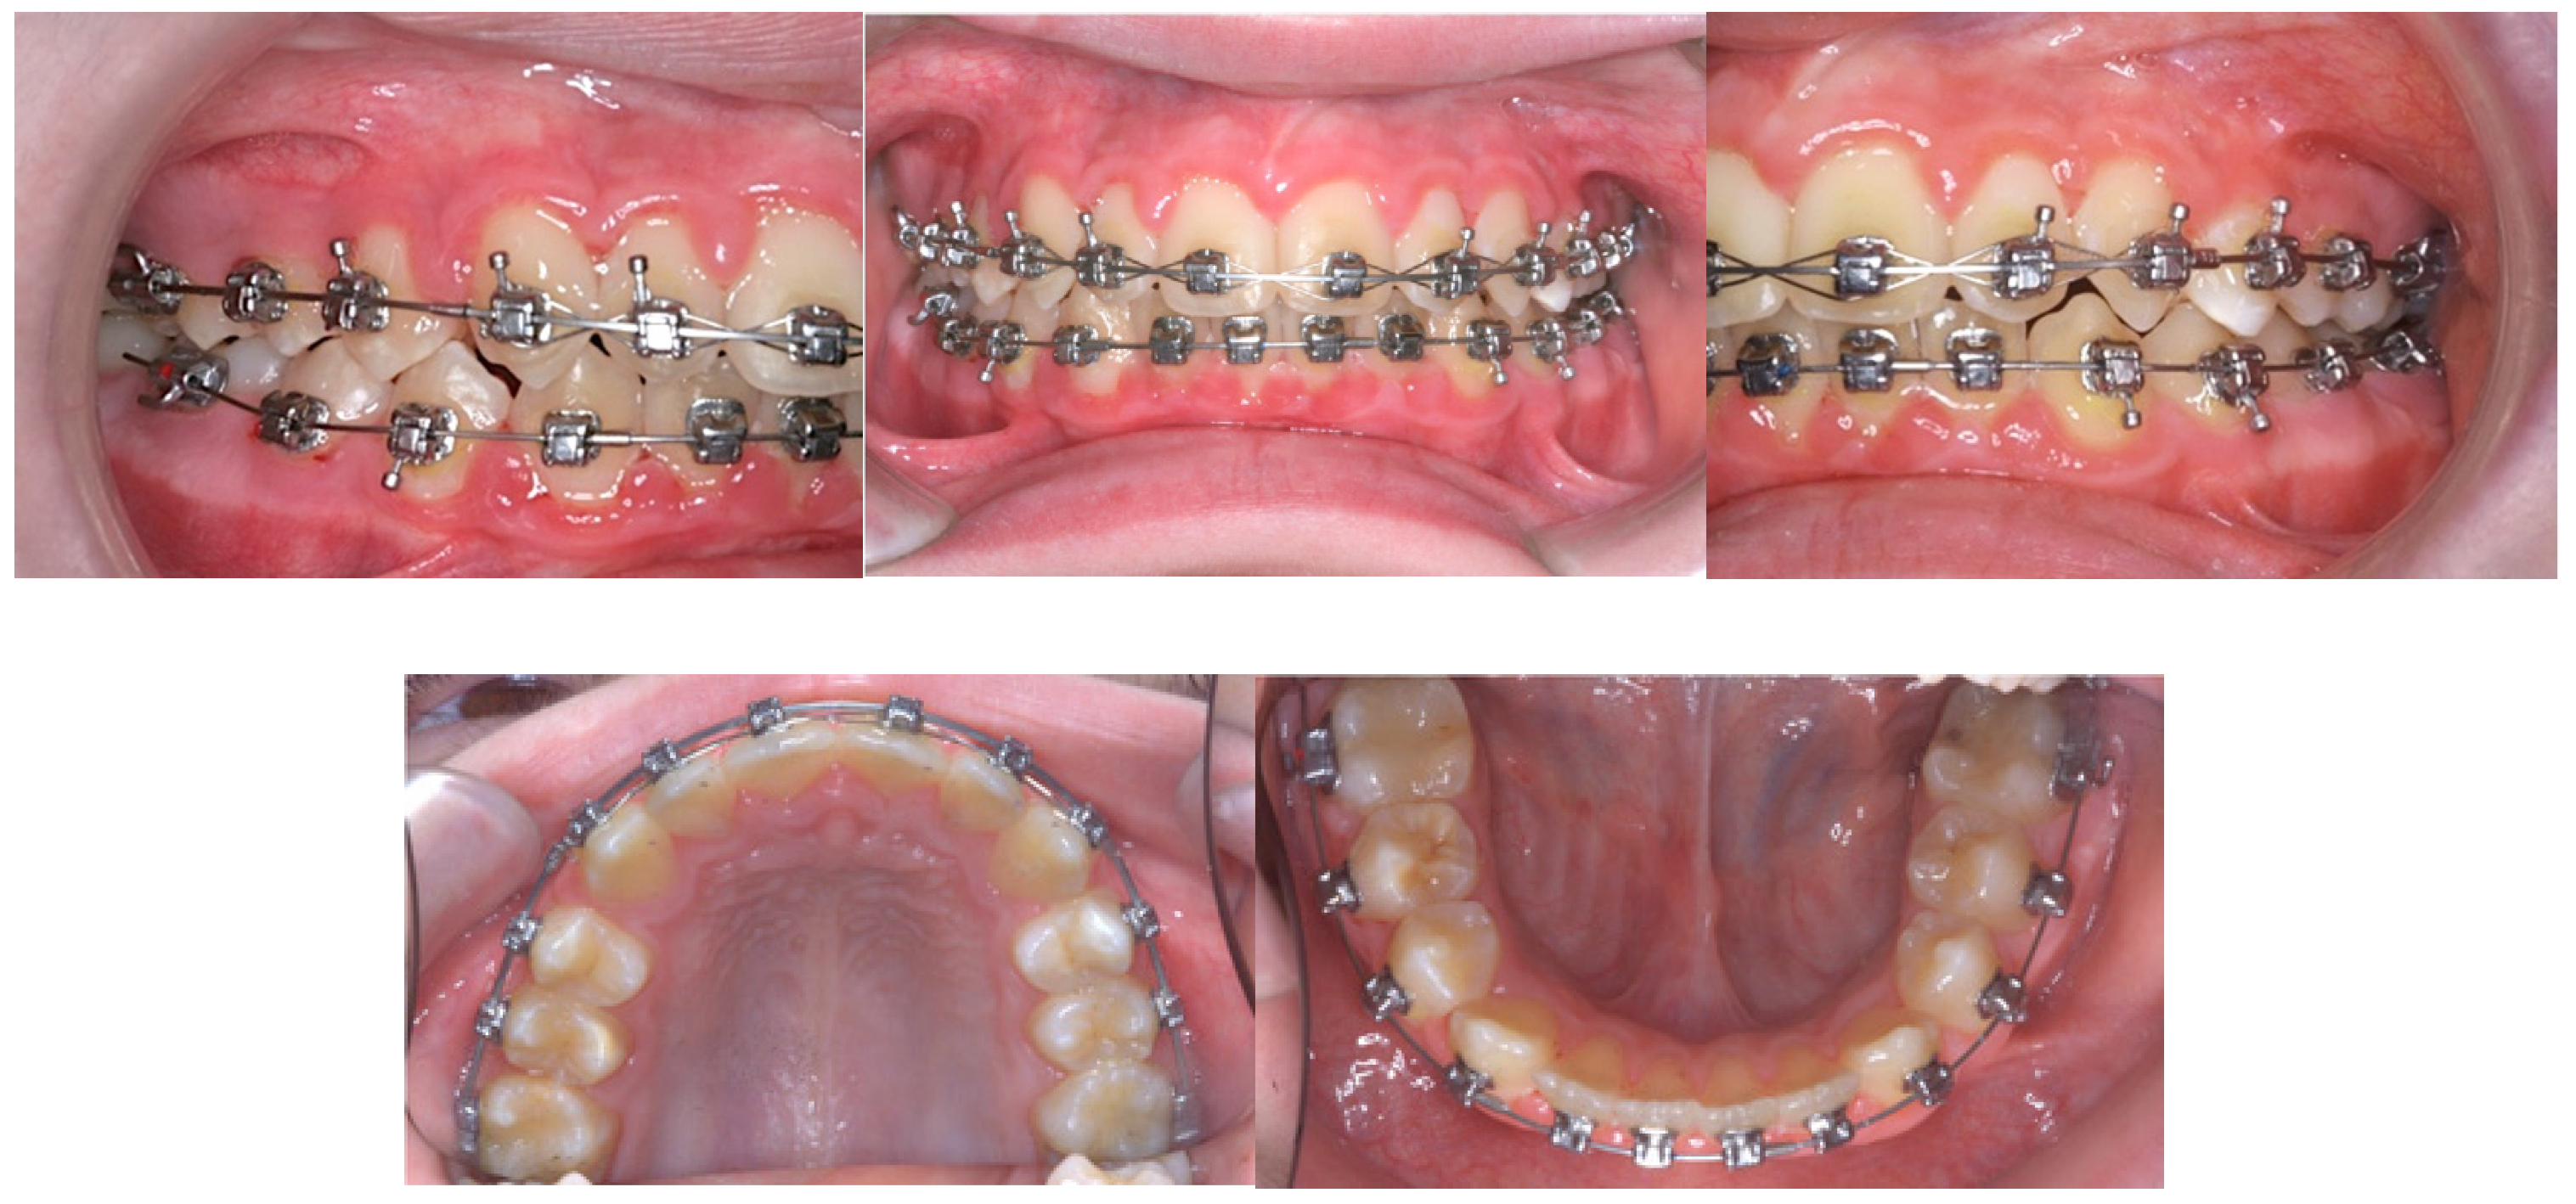

5. Treatment Progress

6. Treatment Results